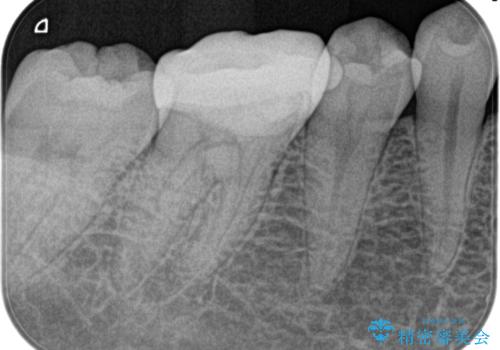

- 奥歯がズキズキ痛いことを主訴に来院されました。

検査の結果、診断を症候性不可逆性歯髄炎、症候性根尖性歯周炎とし抜髄を行っております

根管充填はhydraulic condensation techniqueにて行なっております。

シーラーはWell pulp ST 使用